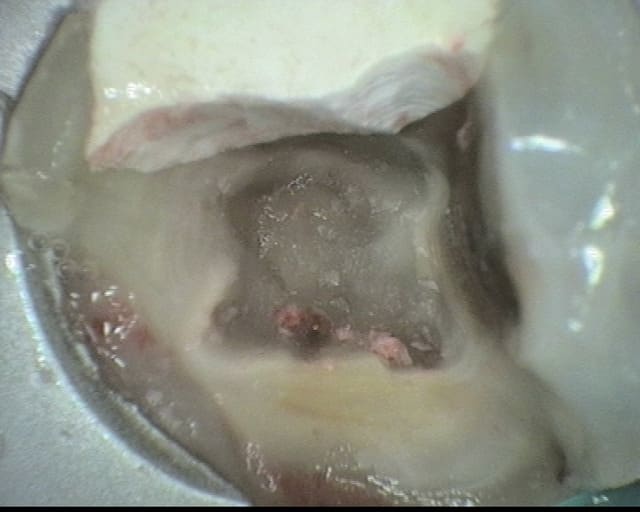

Je profite d'une pause pendant les vacs pour mettre en ligne l'ultime endo avant les vacances estivales (37).

Première effraction du plancher depuis mon diplôme en 2005.

L’éviction des pulpolithes a été réalisée par ultrason. J'ai suivi une coloration entre ce que je pensais être de la dentine réactionnelle et le reste de chambre pulpaire comblée par un gros pulpolithe.

J'ai placé un MTA, CVI par dessus. Je reprends l'endo en septembre.

A votre avis, quels éléments m'ont induit en erreur ? Sur ce type de cas, avez-vous une approche différente ?